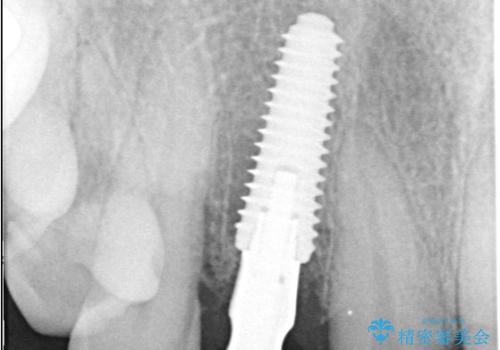

インプラント治療は、低侵襲で短期間に行える「抜歯即時インプラント治療」を選択しました。

この方法は、抜歯したその日にインプラントを埋入し、手術が1回で済むのが大きな特徴です。

治療期間も短く、抜歯からわずか3か月でオールセラミッククラウンを装着することができます。